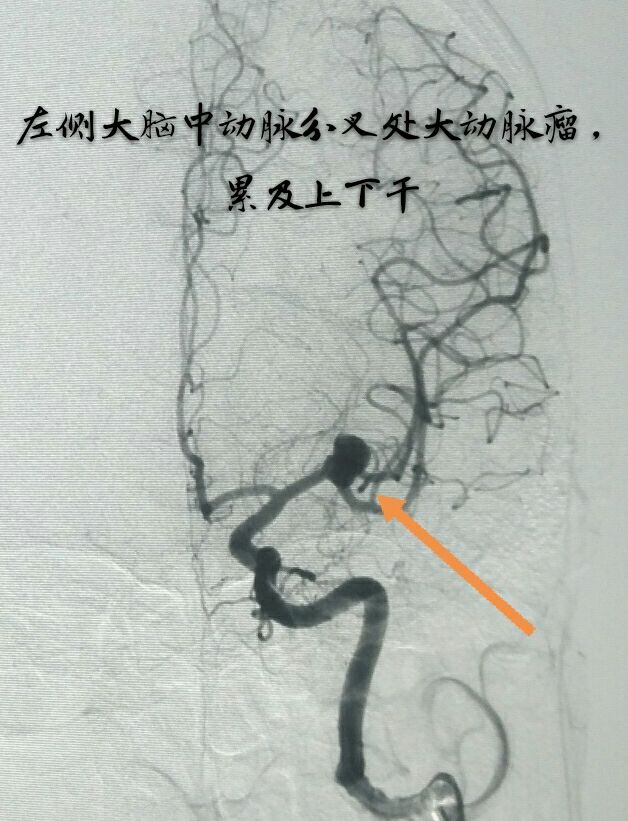

病例九:中年女性患者,间断性头痛3年,DSA示左侧大脑中动脉分叉部动脉瘤,累及上下干

支架辅助下动脉瘤致密栓塞,难点:当时没有3D工作站,动脉瘤与载瘤动脉的关系判断困难,最终通过反复观察3D旋转和造影解决了问题